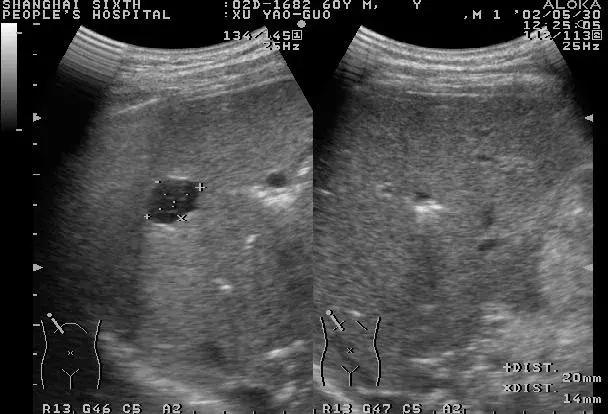

超声检查是肝脏影像学检查首选的方法,具有价廉、便捷、无创等优点。常规超声能显示肝脏大小形态,肝内实质结构、管道系统、血管走向与分布,明确有无肝脏结节、具体的大小与部位、初步鉴别结节的良恶性,适用于常规体检和结节的定期复查。

值得一说的是,随着超声技术的发展,彩色多普勒超声可以诊断直径小于1cm的病变,在有经验的单位,准确率可达90%以上。

发现肝脏结节后,首先要定性论断,即确定病人肝脏占位的性质,是良性还是恶性。

对于B超不能明确诊断的,建议做增强CT扫描或MRI检查,对于高度怀疑肝细胞癌的可行“肝动脉造影”检查。